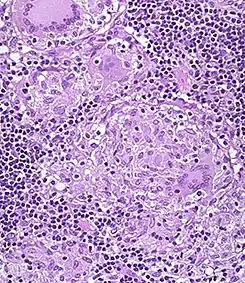

![]() Sección H&E de granuloma no caseado, en el colon de paciente con la enfermedad de Crohn | ||